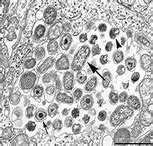

chlamydia psittaci是专性胞内寄生微生物,细胞壁与革兰氏阴性菌相似,对某些抗生素敏感。它的发展周期复杂,包括两种形式。一种(感染性的)基本体附着在宿主细胞上,通过吞噬作用或受体介导的内吞作用进入细胞。吞噬溶酶体融合被早期抑制,初级体重组为网状体,以宿主细胞为能量来源。吞噬小体中含有的这种分裂的网状体通过双融合不断扩大和分裂,形成一种扩大的胞质包涵体,可用Giemsa或免疫荧光抗体染色。扩大和分裂的网状体最终浓缩成基本体,然后从破裂的细胞中释放出来,开始新的循环。